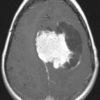

U màng não

» Thông tin: Nam giới – 70 tuổi.

» Lâm sàng: Đau đầu.